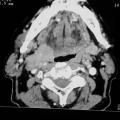

Tumeur de la paroi latérale droite de l’oropharynx

CANCER DES VOIES AERODIGESTIVES

TUMEUR DE LA PAROI LATERALE DROITE DE L'OROPHARYNX